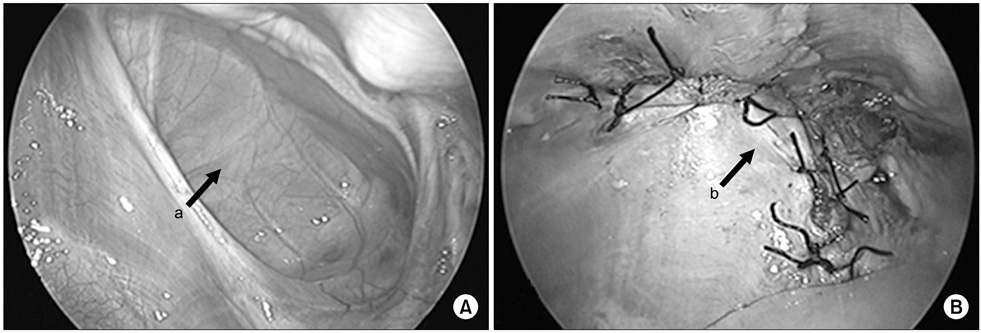

Fig. 3

Esophageal duplication cyst located at posterior mediastinum. (A) The mass was abutting with anterior wall of esophagus on chest CT (2.5×1.9×2.5-cm-sized mass). (B) Mass was connected to muscle layer of esophagus. Arrows: a, mass; b, esophagus.

Fig. 3 Esophageal duplication cyst located at posterior mediastinum. (A) The mass was abutting with anterior wall of esophagus on chest CT (2.5×1.9×2.5-cm-sized mass). (B) Mass was connected to muscle layer of esophagus. Arrows: a, mass; b, esophagus.